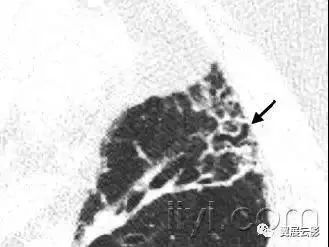

二十五、蜂窝征

病理:蜂窝征代表肺组织的破坏和纤维化,包括大量的囊样含气腔隙和厚纤维壁,是各种肺疾病的晚期改变,已经完全失去了腺泡的解剖结构。囊肿的直径大小从数个毫米到数个厘米,囊壁厚度不一,覆盖以化生的细支气管上皮。

平片和CT:在胸片上,蜂窝征表现为相邻很近的环状阴影,直径主要在3-10mm,壁厚主要在1-3mm,形似蜂窝。这一发现提示肺疾患的终末期。在CT上表现为成簇的囊样含气间隙,其直径大约在3-10mm,偶有大于62.5px的。蜂窝征通常见于胸膜下,具有清晰的壁是其特征,是肺纤维化的CT特征。因为蜂窝征常作为肺纤维化的特异性指标,是常见性间质性肺炎的诊断依据。应当慎用本术语,他可能对病人的治疗产生直接影响。